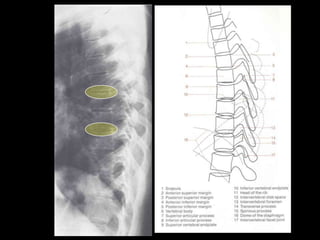

This document provides an overview of normal musculoskeletal imaging. It discusses basic x-ray concepts and densities. It then reviews normal anatomy as seen on x-rays of the skull, spine, pelvis, chest, and extremities. Key anatomical structures are labeled on example x-rays for the shoulder, hip, knee, and foot. Quizzes are included to test recognition of anatomical structures and patient age based on x-rays.